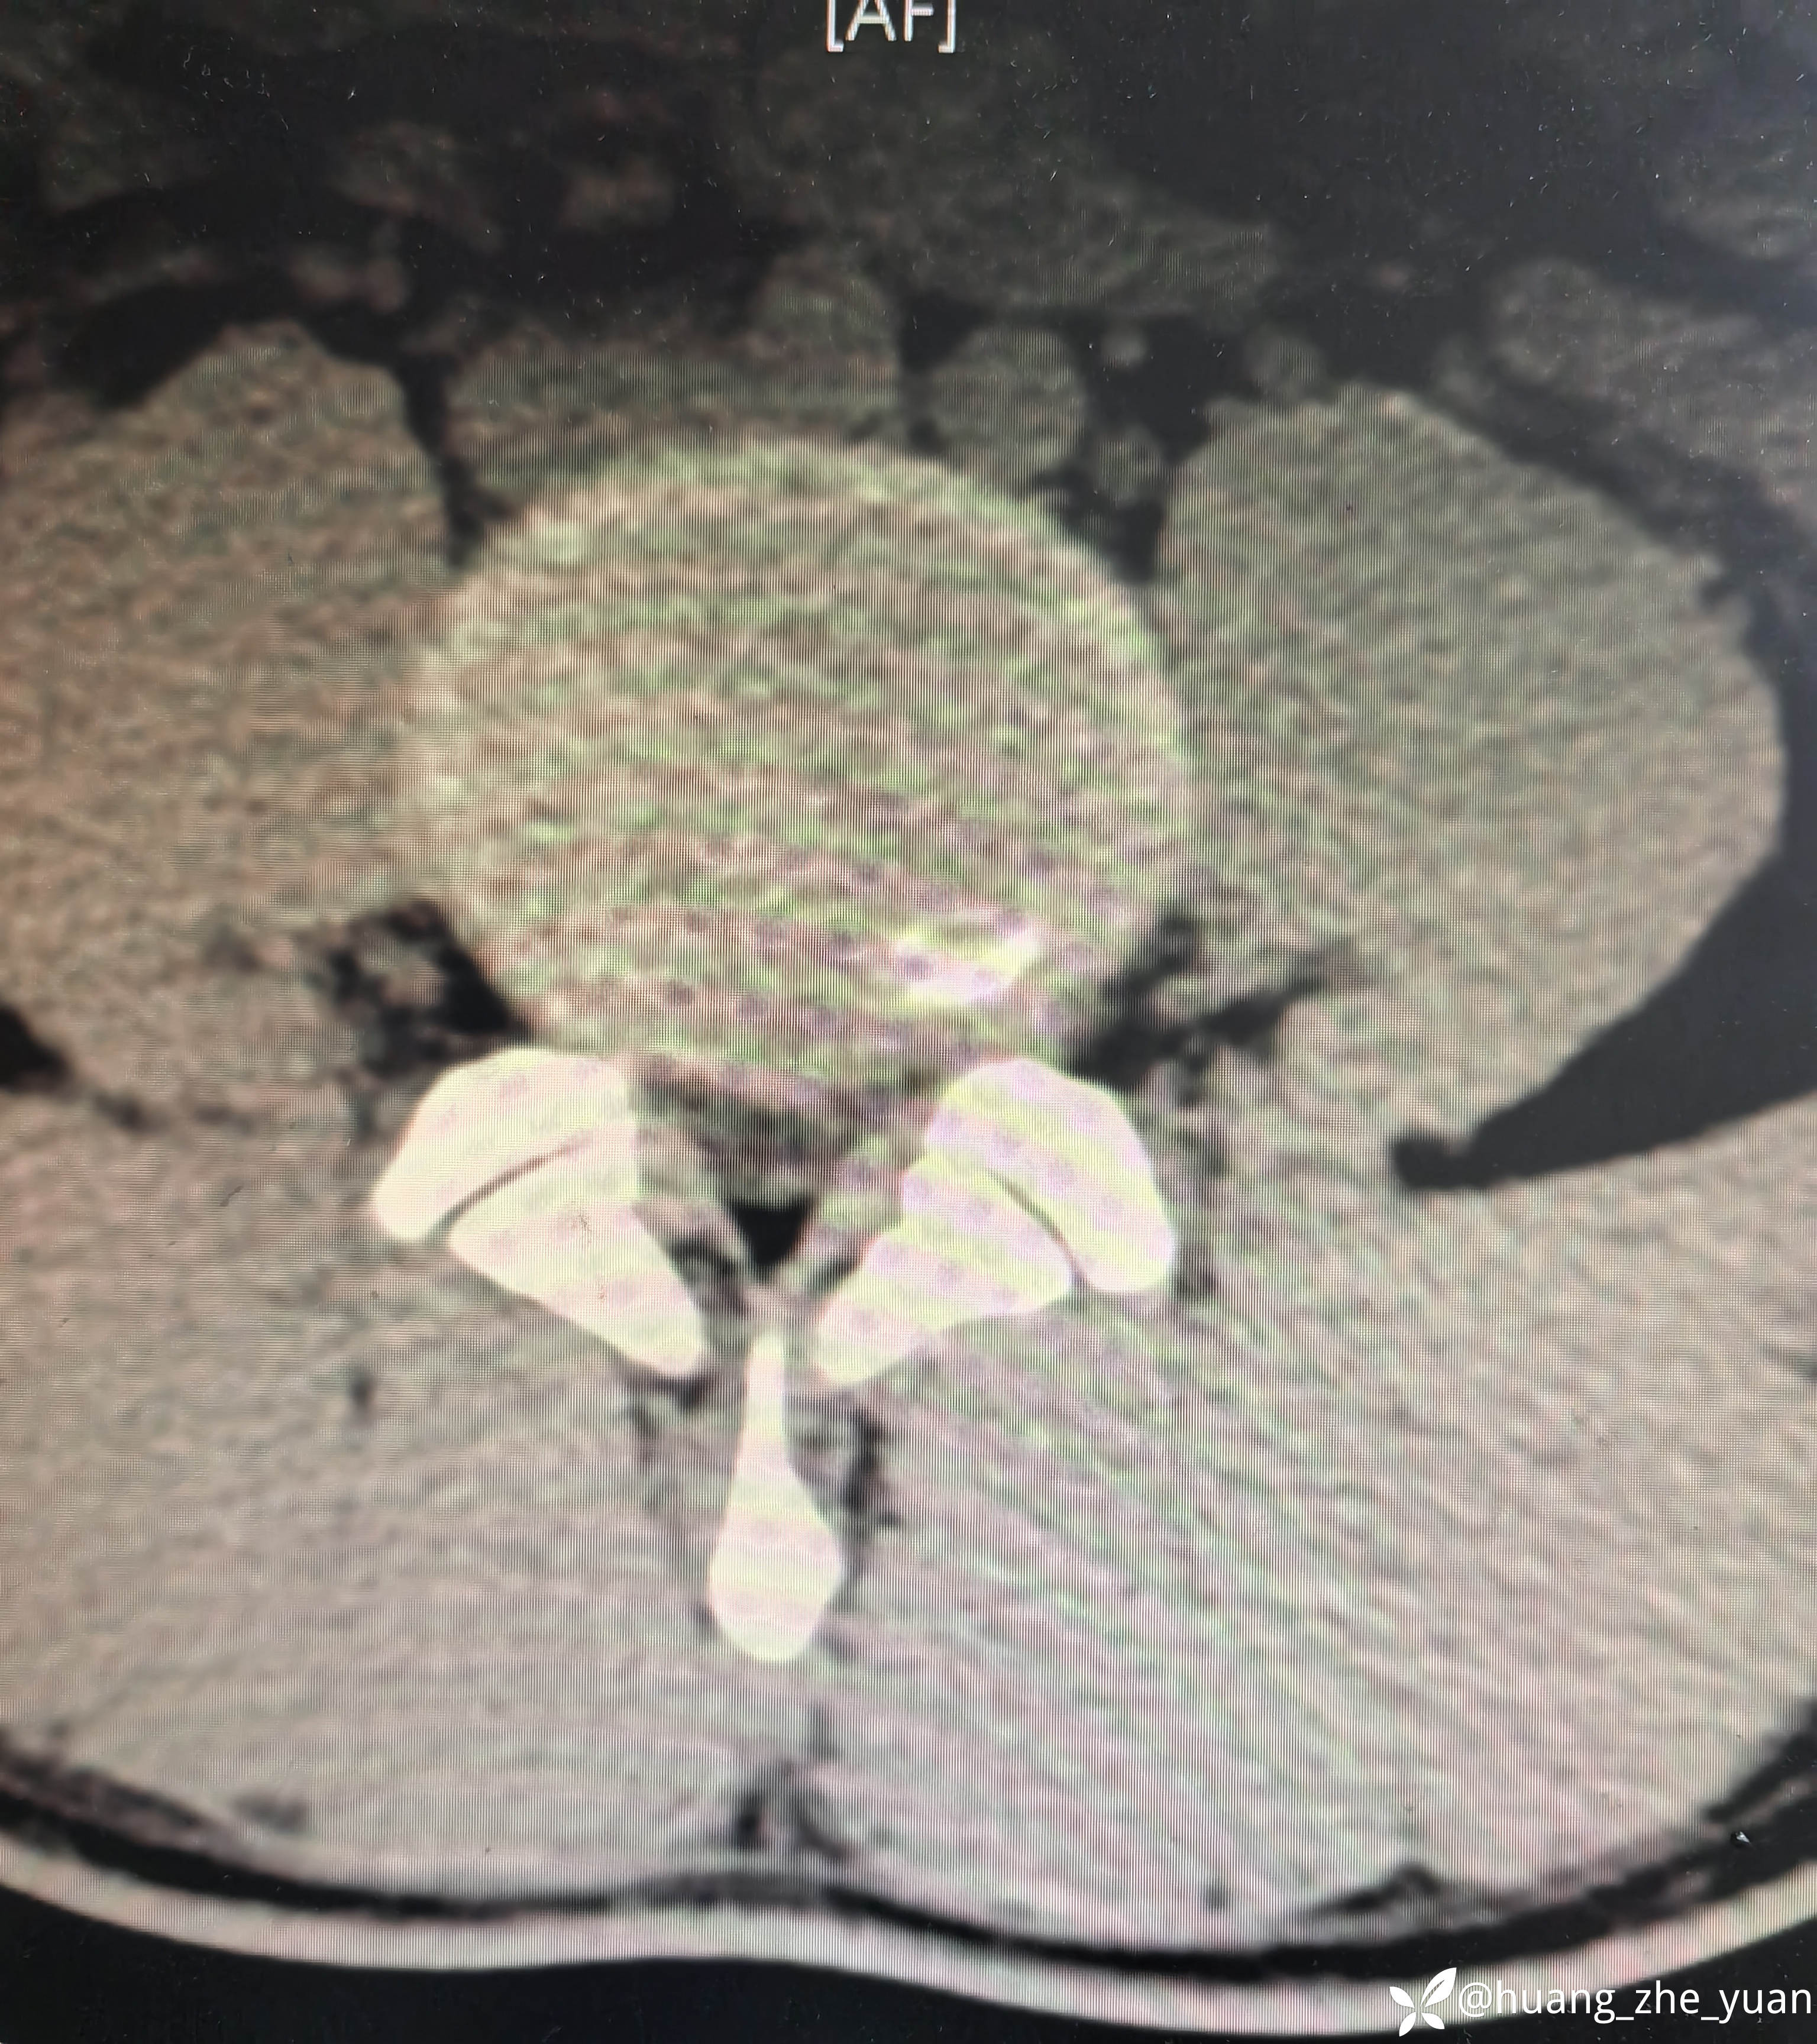

局麻单切口做两节。

椎间孔少量成形。椎间盘做微创消融。